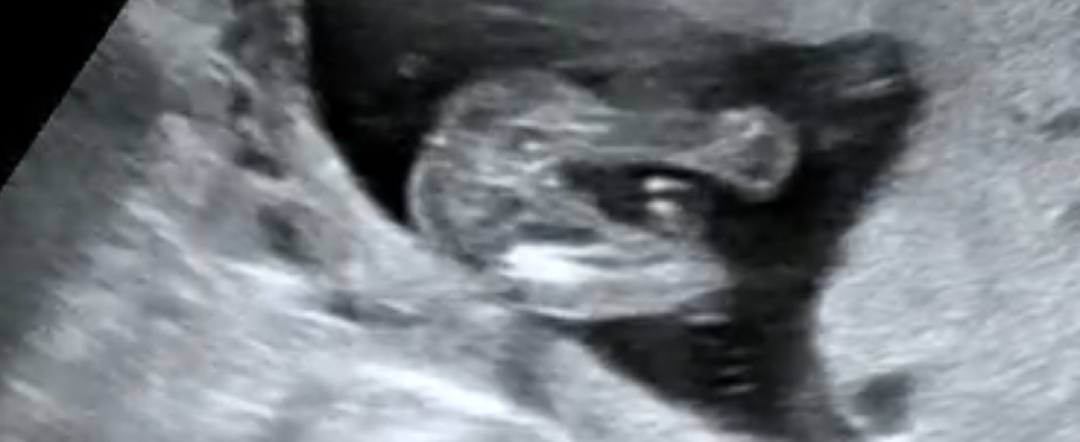

아들일까요? 딸일까요?

16주 2일차에 촬영한 초음파사진이에요! 의사선생님도 긴가민가하시며 70%는 딸인것 같다고 하셨는데 성별반전이 있을 수 도 있다고 하셔서요!! 한 번 봐주시면 감사하겠습니다😭❤️